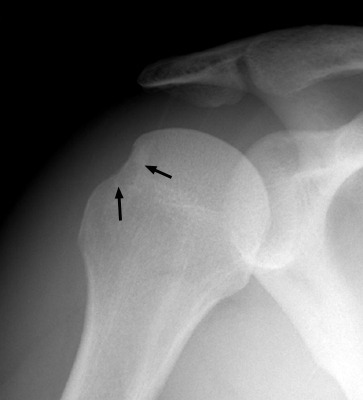

힐-사치 골절(Hill-Sachs fractures) 반가르트 골절(Bankart fractures)은 어깨 전방탈구의 합병증이다. 힐-사치 골절(Hill-Sachs fractures)은 상완골두의 후외측 방면의 결손을 말한다. 전방탈구가 일어나는 동안 상완골두 부위와 전하방 관절와연 사이의 접촉이 있을 때 발생한다. 반가르트 골절(Bankart fractures)은 이러한 외상의 전하방 관절와연의 이차적 골절에 해당한다.

힐-사치 병변 (이미지 출처 : http://www.shoulderdoc.co.uk/article.asp?article=1470)

힐-사치 골절(Hill-Sachs fractures) (이미지 출처 : http://www.gentili.net/fracture.asp?ID=52)